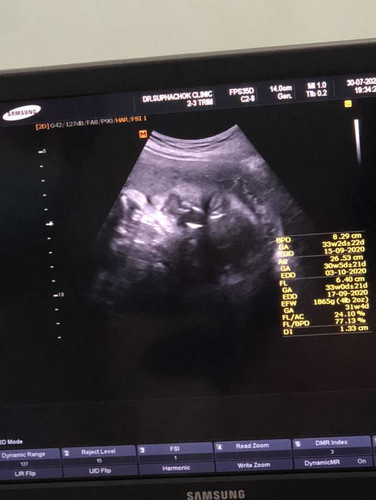

ตอนนี้33week หมอแจ้ง อาจคลอดก่อนกำหนด ประมาณปลายเดือนสิงหา ตอนแรกตัดสินใจว่าจะผ่าคลอด แต่ถ้าผ่าหมอแนะนำคือหลังวันที่4กันยา กำหนดคลอด18กันยา ตอนนี้หมอก็เลยนัดตรวจครรภ์ถี่ขึ้น